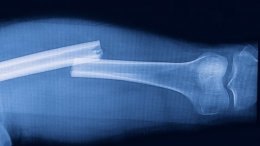

Например, биокерамика (гидроксиапатит) используется в качестве каркаса для костей. Однако данный материал довольно хрупкий и может откалываться по кускам. Куски попадают в мягкие ткани и вызывают воспаление. А вот природные материалы вроде иголок морского ежа обладают большими преимуществами. Они пористые и одновременно очень прочные.

Ученые обратились к гидротермальной реакции, превратив иголки в биоразлагаемые магнийзамещенные трикальцийфосфатные каркасы. При этом была сохранена изначальная пористая структура иголок. Эти каркасы можно спокойно нарезать и сверлить. Тесты на кроликах и собаках показали: клетки костей и питательные вещества легко проходили через поры в каркасе, способствуя формированию костной ткани. Каркас, что важно, легко разлагался по мере того, как его замещает новая кость. Был создан материал из иголок морского ежа.